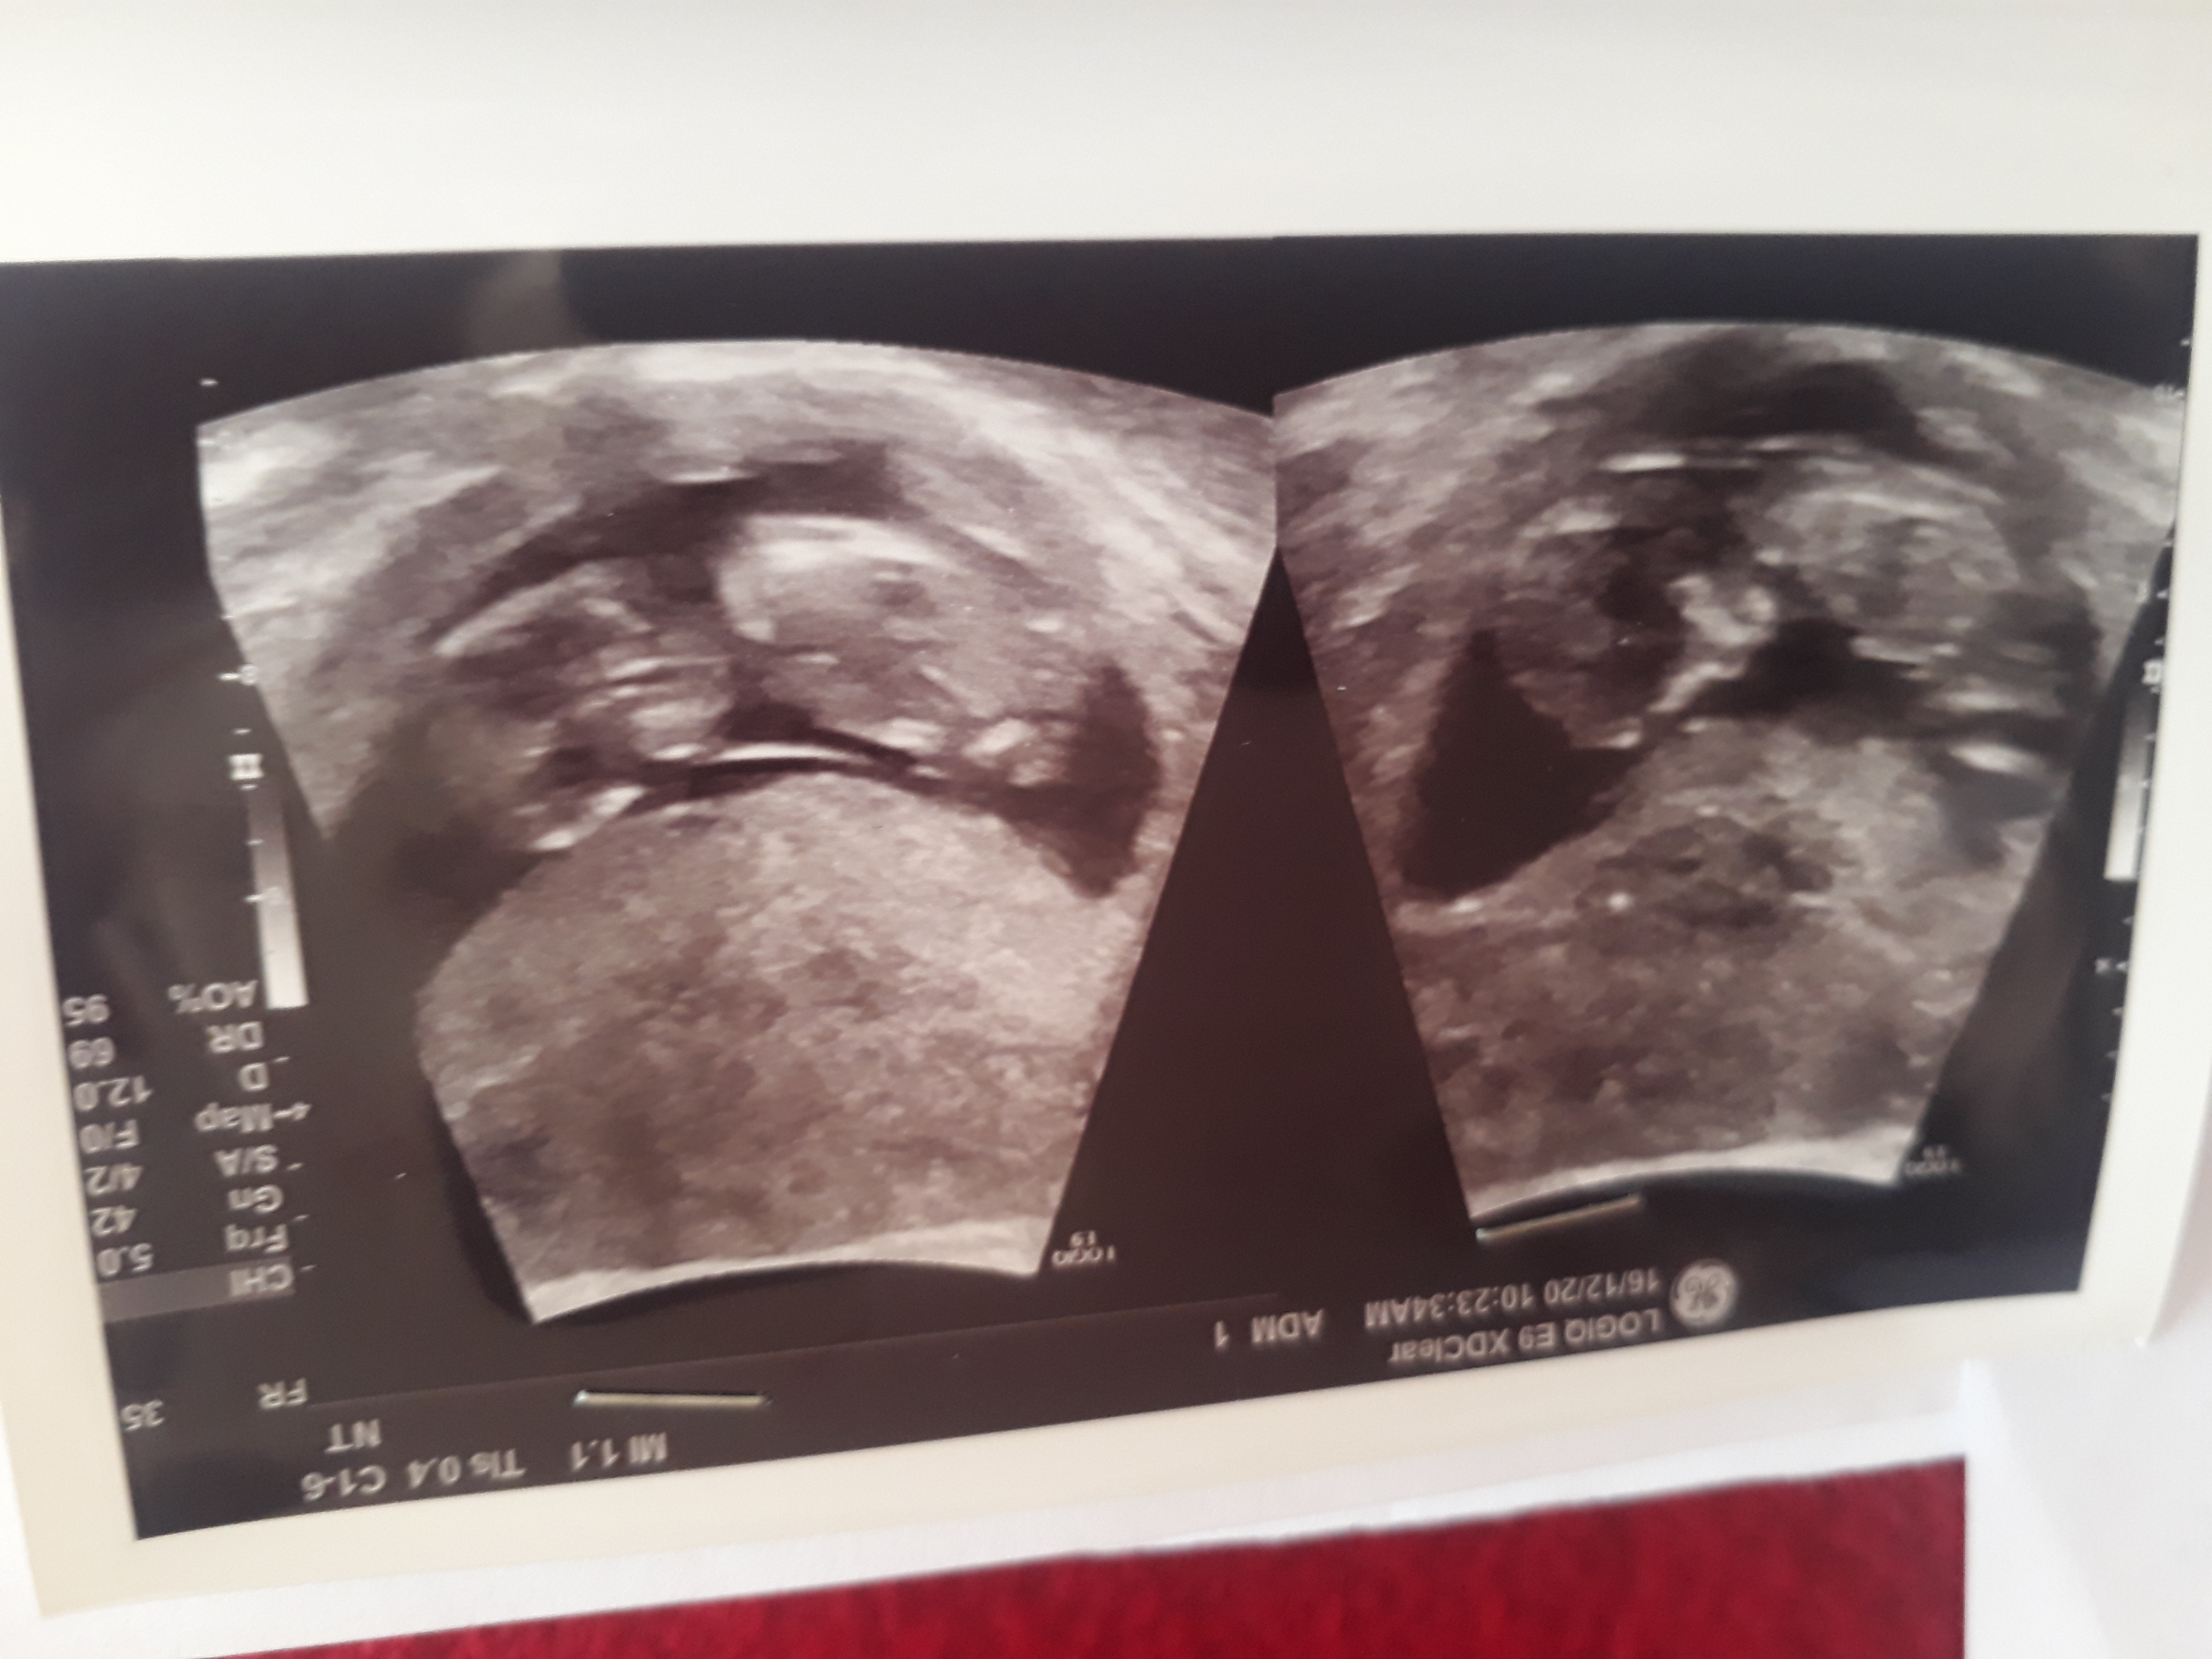

تشخیص جنسیت با عکس سونو

سلام خانوما کسی میتونه از روی عکس سونو حدس بزنه جنسیت چیه؟